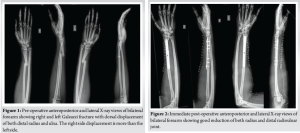

A 39-year-old male presented to the emergency department after being involved in a high-speed motorcycle collision. He was thrown from his motorcycle, landing on both outstretched arms. He reported severe pain, swelling, and deformity in both forearms. Despite the extent of his injuries, he remained hemodynamically stable and had no neurovascular deficits in either limb. On physical examination, gross deformities and tenderness were observed over both distal radii. Radiographs confirmed bilateral Galeazzi fractures with dorsal displacement of the distal radius and ulna fragments, a pattern not previously classified in the Walsh system [7] (Fig. 1).

Galeazzi fractures occur due to axial compression combined with rotational forces acting on the wrist [10]. The radius, being the primary load-bearing bone in the forearm, is particularly susceptible to fractures under these conditions. Disruption of the DRUJ occurs due to tension imbalances in the triangular fibrocartilage complex, a key stabilizing structure [1]. High-impact trauma, such as motorcycle accidents, is a frequent cause of these injuries. The transition zone between the radial shaft’s thick cortical bone and the thinner metaphyseal bone predisposes this region to fractures [2]. The bilateral nature and dorsal displacement of both distal radius and ulna fragments in this case represent an unclassified variation within the Walsh system (Fig. 1). The Walsh classification [7,10] categorizes Galeazzi fractures as follows: